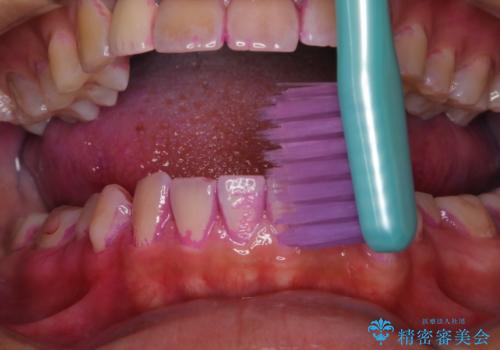

まずは、お口全体の染め出しをし、どこに汚れや磨き残しが多くついているかを明確にしました。その後、普段の歯磨きの仕方の確認や、ブラッシング指導をしました。

10年ぶりの歯科医院へ来院とのことで全体的に汚れ(バイオフィルムや着色)が多く付着してたため、自費クリーニングPMTC60分コース10000+TAXを行いました。

バイオフィルムやステインを取り除くと、ご自身本来の歯の色となります。